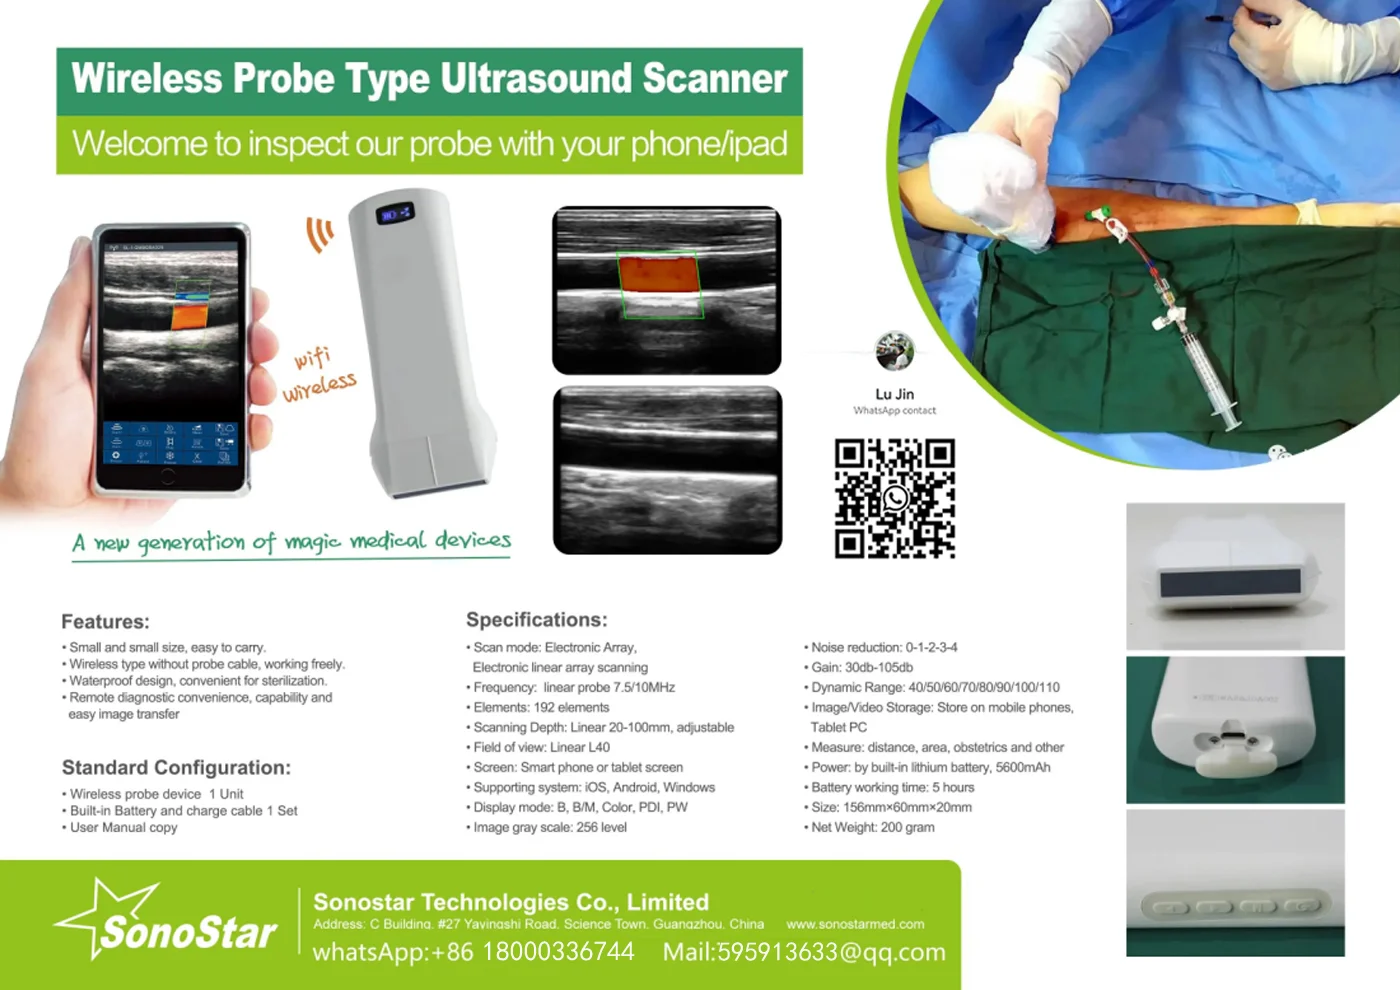

Linear Probe Parameters

-Scanning mode: Electronic array

-Display mode: B, B/M

-Probe element: 80

-Channel of RF circuit board: 16

-Frequency: 7.5MHz/10MH

-Scan depth: 20/40/60/100mm

-Head width: 40mm

-Image Adjust: BGain, TGC, DYN, Focus, Depth, Harmonic, Denoise, Color Gain, Steer, PRF

-Cineplay: auto and manual, frames can set as 100/200/500/1000

-Puncture assist function: the function of in-plane puncture guide line, out-of-plane puncture guide line, automatic blood vessel measurement.

-Measure: Length, Area, Angle, heart rate, Obstetrics

-Image save: jpg, avi and DICOM format

-Image frame rate: 18 frames / second

-Battery working time: 3~5 hours(according to different probe and whether keep scan)

-Battery charge: by USB charge or wireless charge, take 2 hours

-Dimension: 156×60×20mm

-Weight: 220g~250g

-Wifi type: 802.11g/20MHz/5G/450Mbps

-Working system: Apple iOS and Android, Windows 10 system

Linear Probe Pictures:

This machine can be used for both humans and animals: